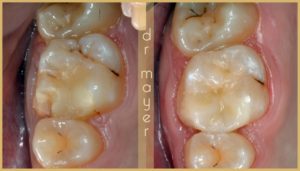

A következő eset egy szerencsésen letört fogat mutat be, amit Gradia betéttel láttunk el:

A kép bal oldalán egy teljesen letört csücskű felső első nagyörlő látható. A kép jobb oldalán pedig ugyanaz a fog betéttel helyreállítva.